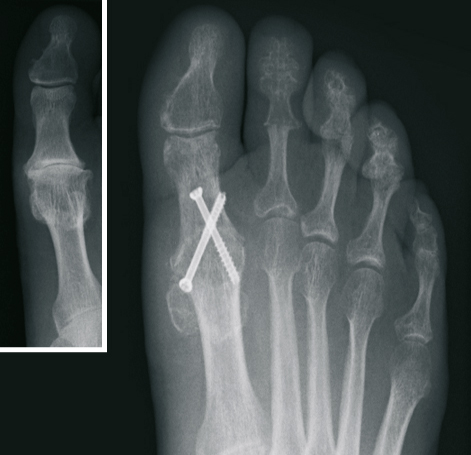

The Hallux valgus (balltoe)

Surgical correction without the presence of pain is not advisable from a purely cosmetic point of view. However, In case of pain in the big toe, the operative procedure is the only permanent therapeutic option.

After extensive examination, consideration of individual needs, as well as analysis of the X-ray images, the treatment is determined. Different internationally recognized surgical procedures are used. We use modern plates and titanium screws.

Depending on the extent of surgery and the procedures to be applied, we have the ability to perform both an outpatient and inpatient treatment.